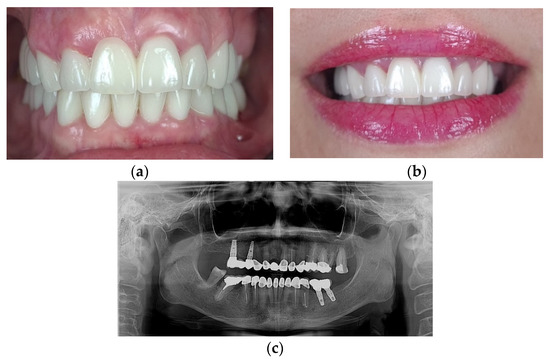

Full-Mouth Rehabilitation of a Patient with Gummy Smile—Multidisciplinary Approach: Case Report

2. Case Report